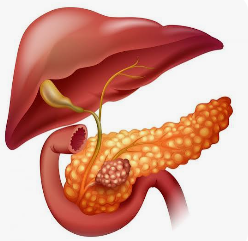

El Cáncer de páncreas es un cáncer que se origina en los tejidos del páncreas, un órgano ubicado detrás del estómago que participa en la digestión y en la regulación del azúcar en la sangre. El tipo más frecuente es el Adenocarcinoma ductal de páncreas. Síntomas En...